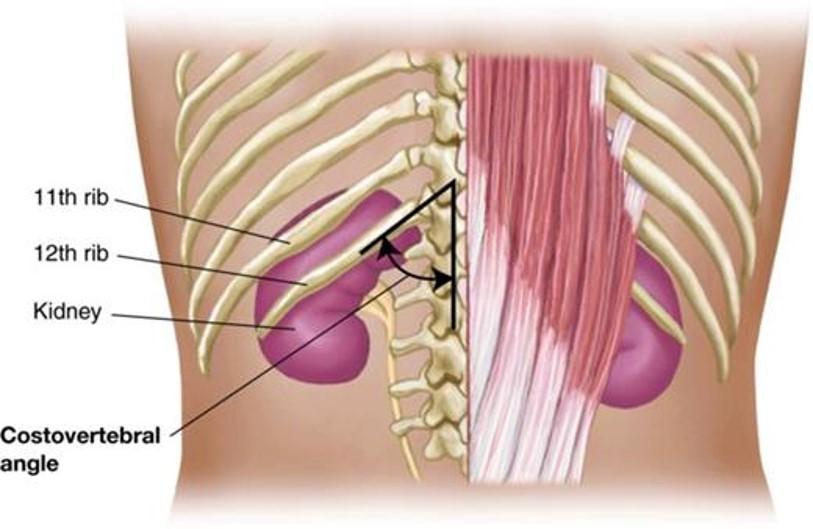

Identify 2 bony landmarks of the posterior thorax

- What is “CVA tenderness”?

Spinous processes of thoracic vertebrae 1 -12

Costovertebral angle (CVA)

- Clinical: “CVA tenderness”: a medical test in which pain is elicited by percussion of the area of the back overlying the kidney...The test is positive in people with an infection around the kidney